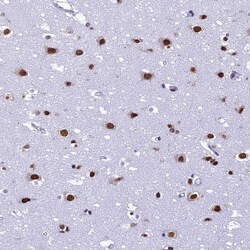

Supportive validation

- Submitted by

- Invitrogen Antibodies (provider)

- Main image

- Experimental details

- Immunohistochemical analysis of PRAMEF12 in human cerebral cortex using PRAMEF12 Polyclonal Antibody (Product # PA5-60974) shows strong nuclear positivity in neuronal cells.